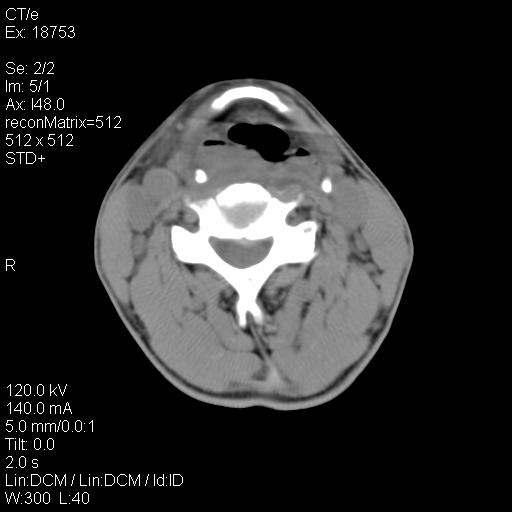

标题: CT21693:男 58岁 右侧咽部疼她2天余 PE:右侧扁桃体肿大 压痛 [打印本页]

标题: CT21693:男 58岁 右侧咽部疼她2天余 PE:右侧扁桃体肿大 压痛

右化脓性扁桃体炎症伴咽后壁脓肿形成.

以下是引用zjzjr在2009-8-19 21:07:00的发言:[br]右化脓性扁桃体炎症伴咽后壁脓肿形成.